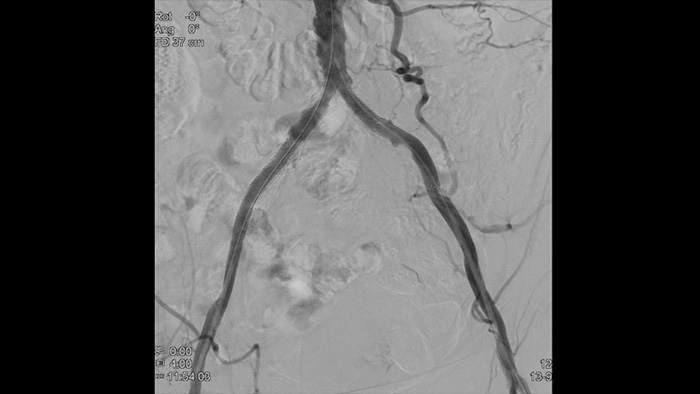

2D DSA with ClarityIQ technology

2D DSA with ClarityIQ

Visualises high-definition images of vessels with outstanding vascular detail to support precise treatment strategies, navigation and follow-up.